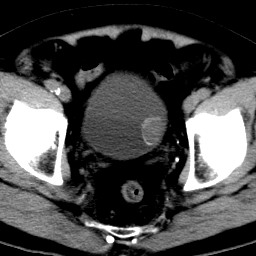

男,79岁,无痛性肉眼血尿1周。

由膀胱左侧后壁向内突出一圆形肿物,边缘光滑伴钙化,内密度均匀。支持考虑:膀胱癌!

蛋壳样钙化------应该是良性病变的影像表现。期待病理。

膀胱ca并肿瘤表面钙质沉积

膀胱左后侧壁可见软组织块影宊向腔内,边缘钙化,考虑膀胱占位,癌可能性大。

术后病理示:膀胱乳头状癌。